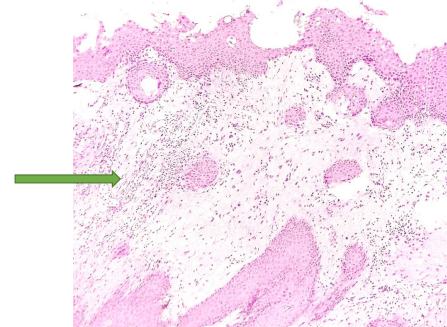

Dense inflammatory infiltrate (arrow) on Hematoxylin-Eosin stain. (Magnification 40X)